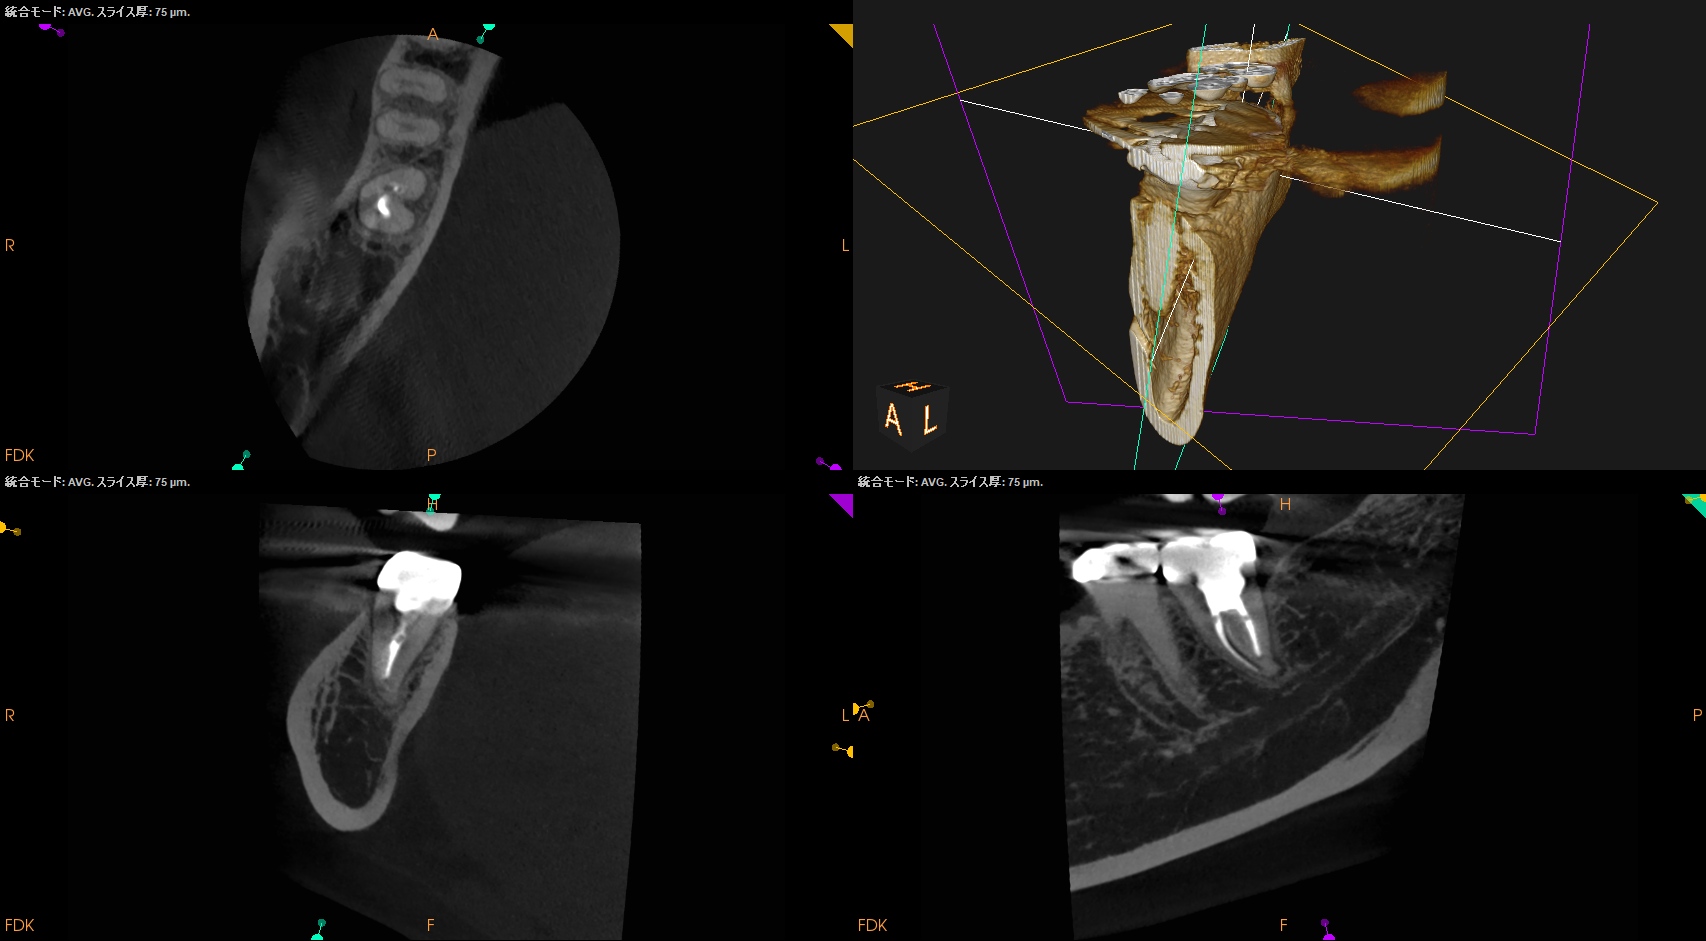

CBCT(2024.9.9)

#31 M

#31 D

根尖病変は無いようだ。